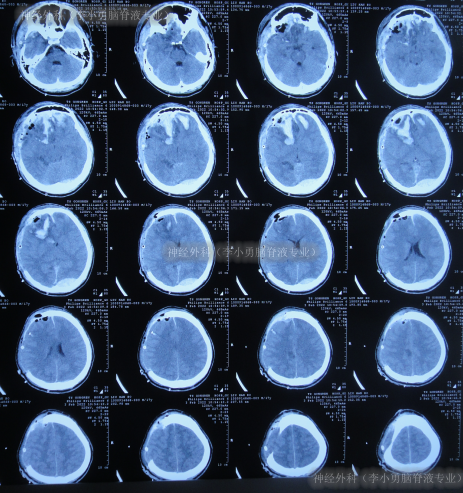

虽又再次出现脑积水但2022年5月5日(脑室腹腔分流术后38天),仍进行了右侧额颞顶部颅骨缺损修补术(图-12)。

图-12:2022年5月6日头颅CT

但颅骨修补术后1周即2022年5月13日(脑室腹腔分流术后45天),患者反而出现意识变差,由清醒变为嗜睡,肢体活动也变差,且肢体肌张力增高,查头颅CT(图-13)后给予保守治疗。

图-13:2022年5月13日头颅CT

该院继续治疗半月,但患者病情进一步加重为昏迷,期间3次查头颅影像(图-14)。

图-14:3次查头颅影像

因昏迷加重于2022年6月2日(颅骨修补术后27天即脑室腹腔分流术后65天),查头颅CT示仍脑积水(图-15);进行了腰椎穿刺示颅压较高。

图-15:2022年6月2日头颅CT

因昏迷不断加重,于是家属找到北京北亚骨科医院的神经外科(李小勇脑脊液专业)。